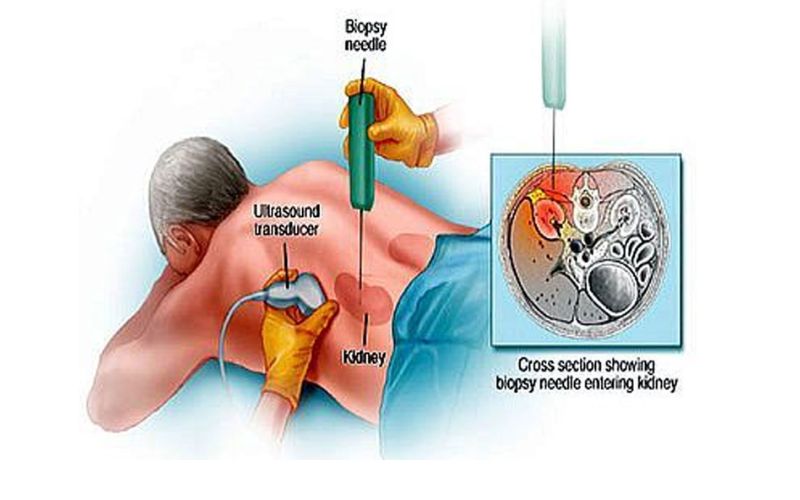

Kidney biopsy

A kidney biopsy is a diagnostic procedure where a small sample of kidney tissue is extracted to examine under a microscope. It helps determine the cause, ,